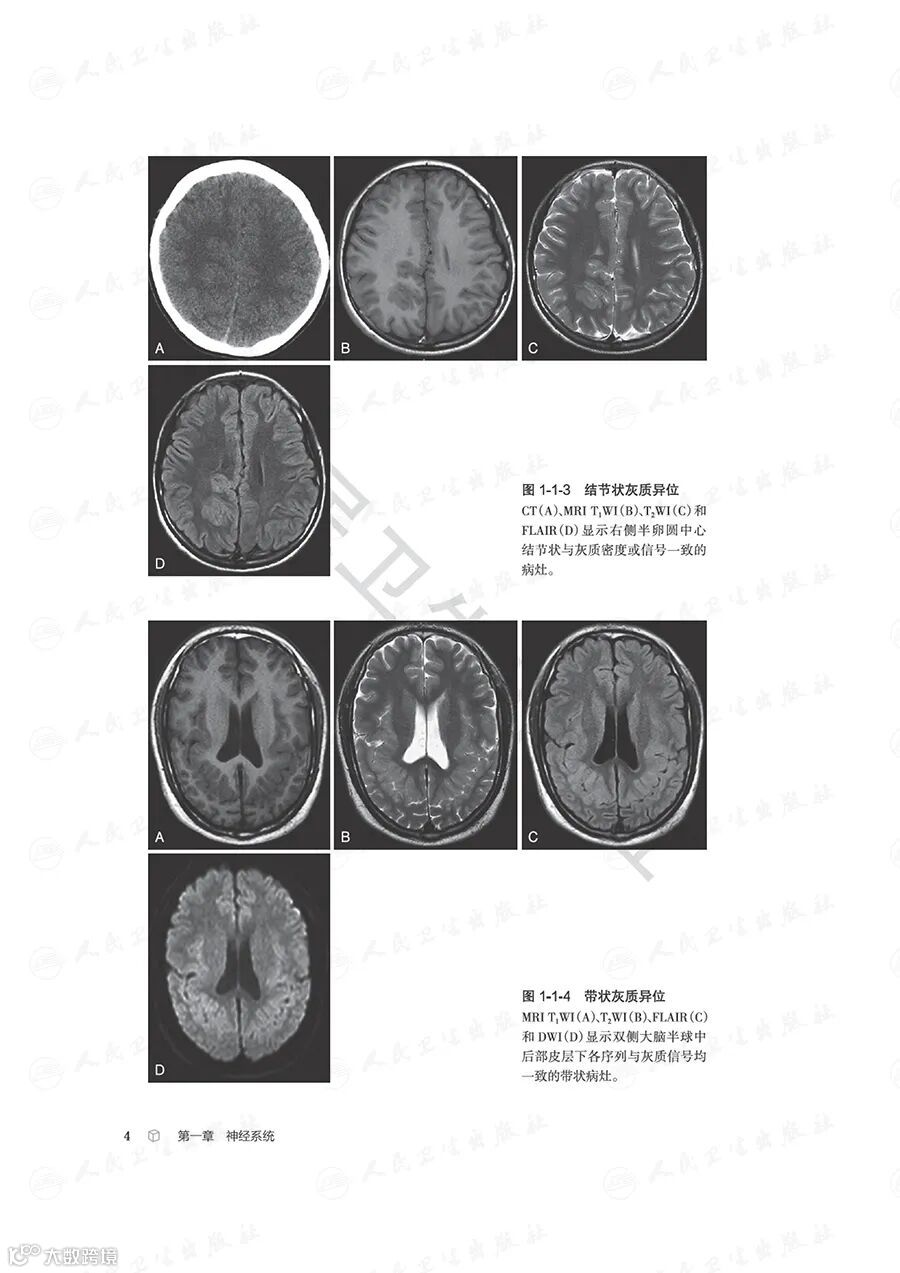

本书紧扣影像科医师日常执业场景,依托中华医学会放射学分会青年学组“青影智慧-影像诊断思维系列培训课程”的核心体系,全面汇总并梳理了临床影像诊断中高频出现的近300个典型征象,覆盖神经系统、头颈五官、呼吸、心脏大血管、乳腺、消化、泌尿、生殖、骨关节等九大核心诊疗领域。

全书以影像征象为核心切入点,深入剖析并提炼各征象的特异性影像学表现,辅以典型病例图像直观佐证;借助思维导图清晰可视化征象分析与诊断推导的完整脉络,同步融入鉴别诊断的关键要点及适配疾病谱系。通过层层拆解、去芜存菁的解析方式,完整呈现从影像征象识别到疾病确诊的全链条思维推演过程,为影像科医师提供极具参考价值的诊断思维范式。

本书旨在为医学专业人士提供系统化的影像诊断思维框架,涵盖了全身各个器官系统的常见疾病。每个章节不仅详尽介绍了各类疾病的影像学特征,还配有诊断思维树和鉴别诊断疾病谱,旨在帮助读者快速而准确地进行影像诊断。这种结构化的方法将使读者在处理复杂病例时更加得心应手。